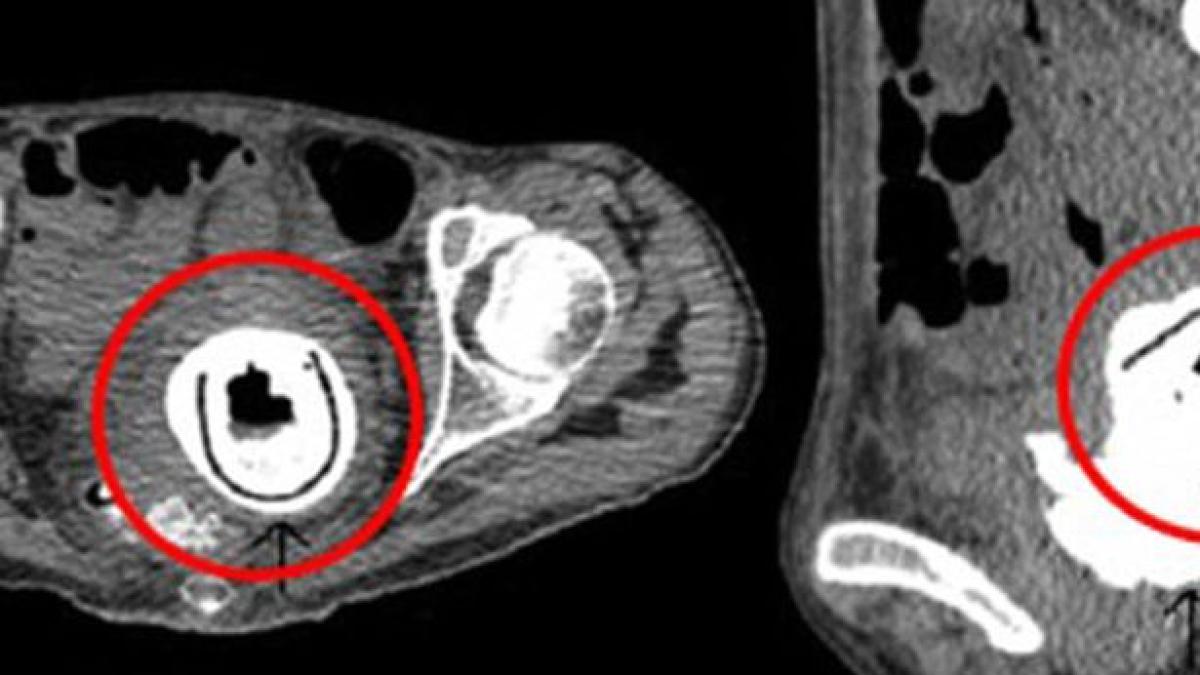

O femeie din Marea Britanie s-a dus la medic pentru că se simțea obosită tot timpul. Medicii au fost șocați să descopere că femeia avea, de 10 ani, în vagin, o jucărie sexuală.

Femeia, în vârstă de 38 de ani, spune că se simțea obosită și a început să piardă din greutate. După ce medicii i-au făcut raze-x, au descoperit că femeia avea în vagin o jucărie sexuală lungă de 12 centimetri, scrie Miror.

Jucăria a dus la blocaj urinal, iar urina se vărsa în vaginul ei. Medicii spun că viața femeii, a cărei identitate nu a fost dezvăluită, a fost pusă în pericol.